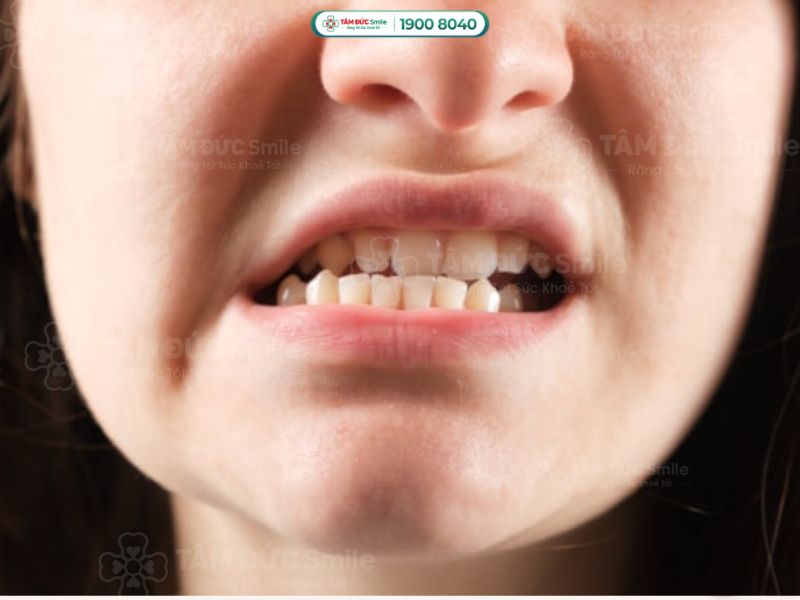

3.2. Răng của bạn mọc chen chúc

Răng mọc chen chúc, không đúng vị trí do thiếu không gian trong hàm. Một số trường hợp chen chúc cần được can thiệp bởi niềng răng là:

- Răng chồng chéo, xô đẩy lẫn nhau làm đau buốt khi ăn nhai.

- Cảm giác khoang miệng bị đầy, các răng mọc lớn, kích thước to.

- Hướng mọc lệch, nghiêng, đâm ngang làm xê dịch răng kế cận.

- Khó vệ sinh khiến hôi miệng, viêm nướu, sâu răng.

Răng mọc chen chúc, không đúng vị trí do thiếu không gian trong hàm